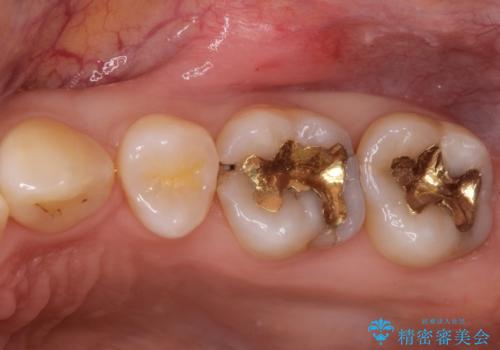

- 他院で虫歯になっていると指摘され来院されました。適合の良いゴールドインレーによる治療がされていましたが、違う部分が虫歯になってしまっていました。審美性の良いセラミックインレーを希望されました。

ゴールドインレーを除去し、その下で広がっていた虫歯をきれいに取り除きました。